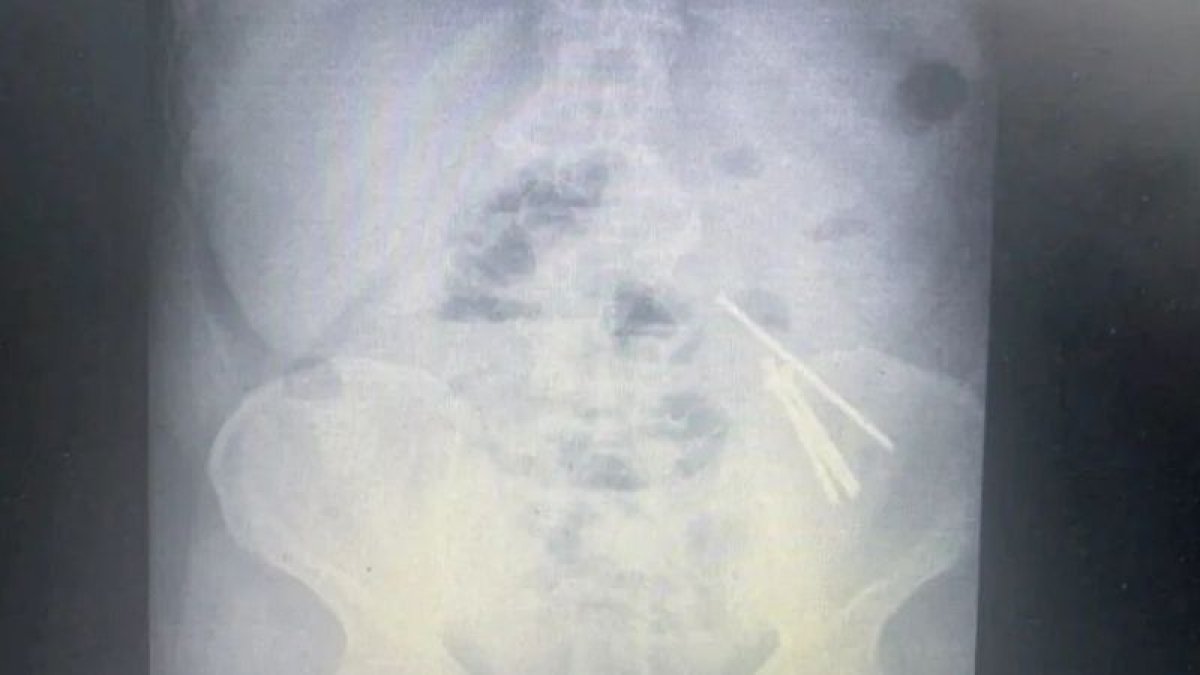

Алматы облысында шизофрениямен ауыратын ер адам ұзындығы 10 см-ге дейін жететін 14 шегені жұтып қойған, деп хабарлайды Zakon.kz.

Хирургтер 39 жастағы ер адамның ішегінен көлемі 10 см-ге дейін жететін, 14 шегені алды.

Хирургия бөлімінің меңгерушісі Марат Әбжановтың айтуынша, мұндай жағдайлардың диагностикасы рентгендік суретке негізделген.

Дәрігер көлемі 10 см болатын 14 шегені алған кезде аш ішектің зақымдалғанын, оның ішінде тесігі бар екенін айтты. Операциядан кейінгі кезең асқынусыз өтті.